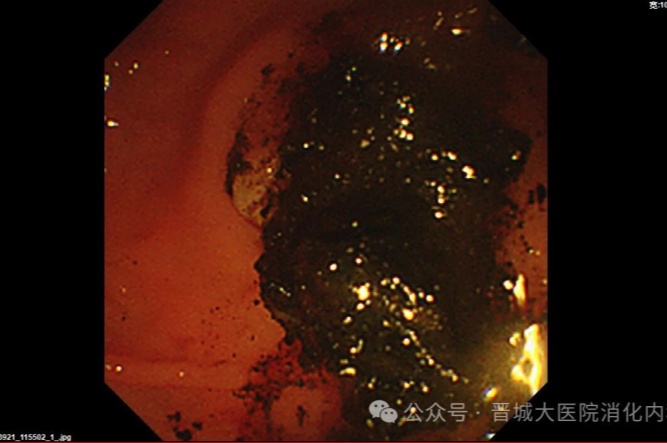

手術(shù)中,普通外科首先為李阿姨行“腹腔鏡膽囊切除”(LC),消化內(nèi)科團(tuán)隊(duì)緊隨其后行ERCP,造影發(fā)現(xiàn)膽總管內(nèi)有多個(gè)巨大結(jié)石,最大約2.5×2.1厘米,且結(jié)石堅(jiān)硬,形如煤渣樣,使用取碎石一體網(wǎng)籃多次反復(fù)碎石、取石。用生理鹽水反復(fù)沖洗膽道,無結(jié)石殘留。利用微創(chuàng)技術(shù)順利完成膽囊切除及膽總管結(jié)石取石,手術(shù)時(shí)間短、創(chuàng)傷小、恢復(fù)快。